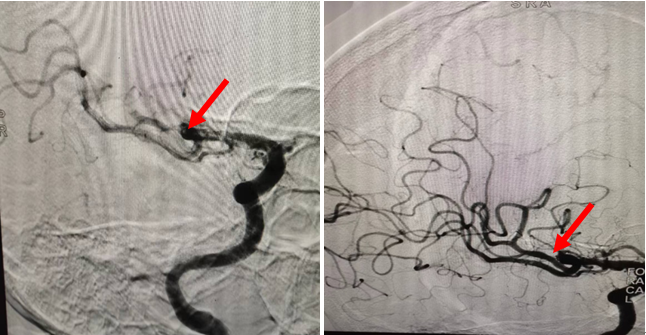

患者为47岁女性,因“认知功能下降伴言语不清3小时余”来我院急诊求治,卒中团队考虑患者急性脑梗死予以静脉溶栓,进一步联合影像科团队通过CTP灌注明确患者存在右侧大脑中动脉M2段上干远端闭塞并存在明显缺血半暗带。神经内科钟小劲主任医师、何伟亮副主任医师、朱敏真副主任医师和温样春主治医师仔细研究判读患者术前大脑灌注图像,认为患者仍存在明显脑组织挽救空间,若不进行处理,会遗留明显的神经系统后遗症,经快速细致讨论确定方案并取得患者家属同意后,患者于急诊行“经皮颅内动脉取栓术”,成功开通了闭塞血管,效果显著,患者恢复良好,未遗留明显高级神经智能活动障碍,术后获得了患者和家属的一致认可。

神经内科介入团队